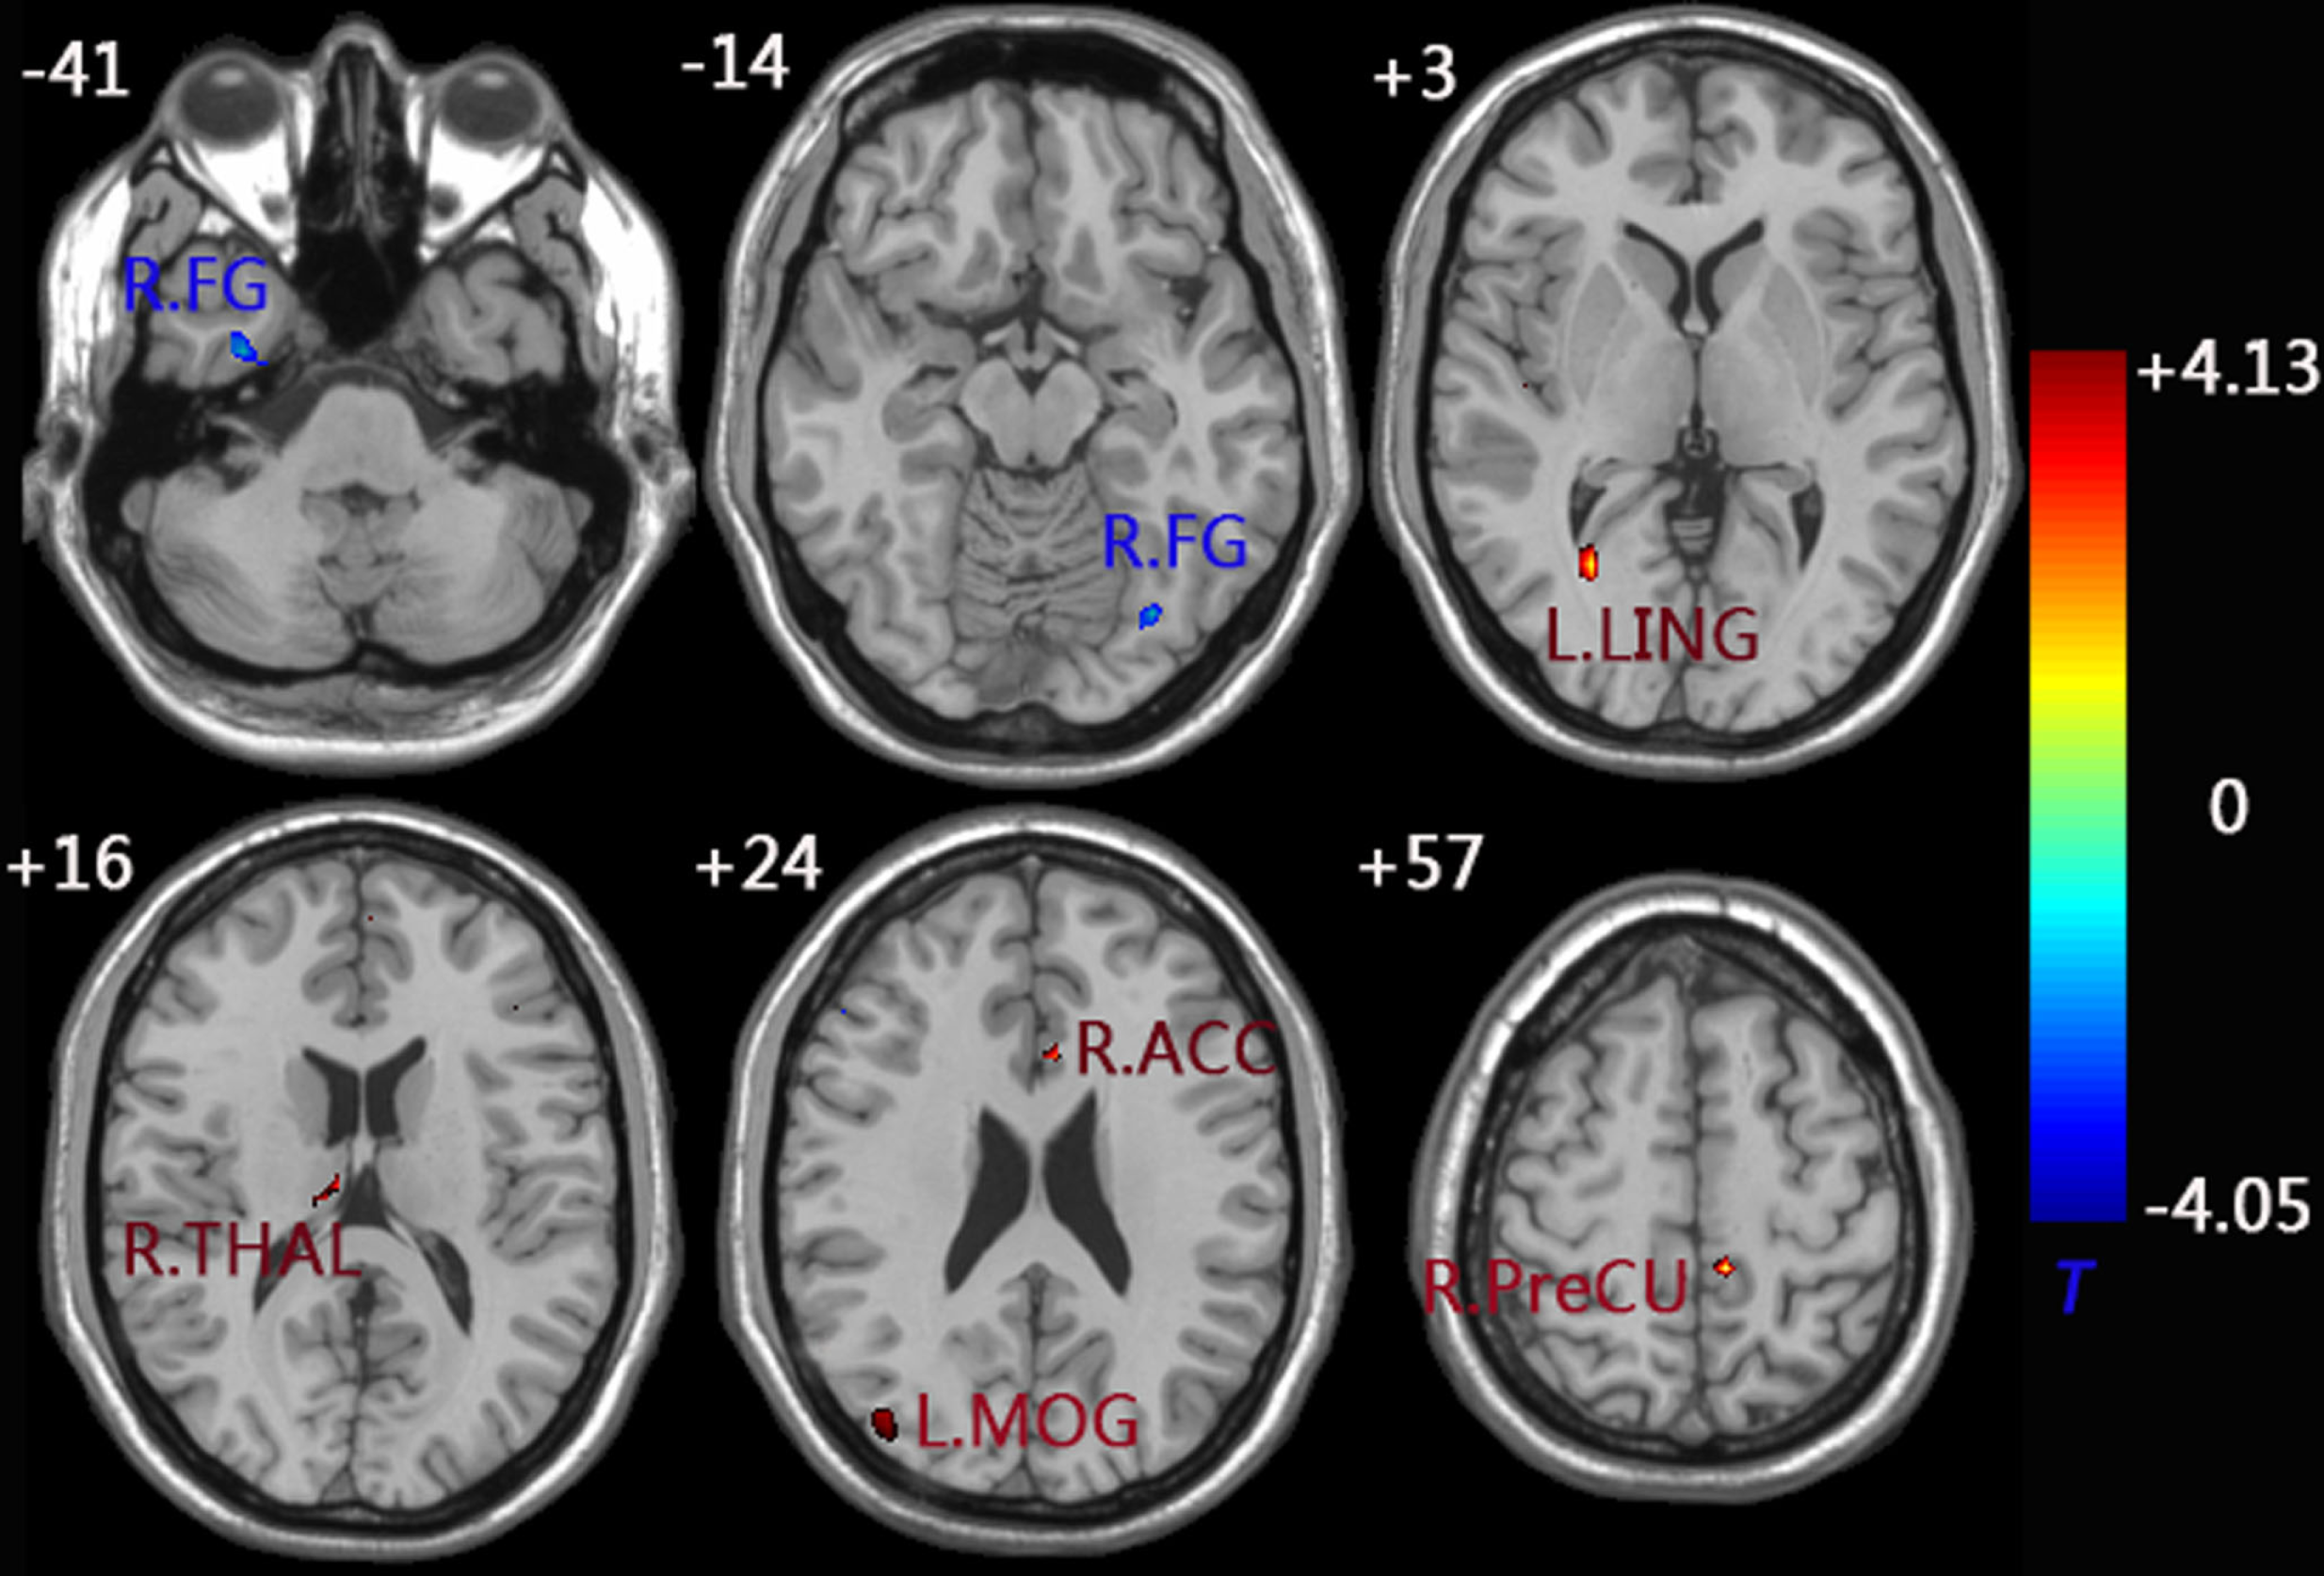

When compared to the control group, the aMCI group demonstrated decreased functional connectivity between the left FG and right FG. In comparison, increased functional connectivity was observed between the left FG and a group of brain regions including the left MOG, left LING, left PreCU, right ACC, and right thalamus (THAL) (Figure 3 and Table 3).

Figure 3

functional connectivity difference maps of the left FG between the aMCI and control group; (P < 0.01, 28 voxels, corrected for multiple comparisons). Abbreviations: FG, fusiform gyrus; MOG, middle occipital gyrus; LING, lingual gyrus; PreCU, precuneus; ACC, anterior cingulate cortex; THAL, thalamus; L, left; R, right.

Similarly, decreased functional connectivity between the right FG and brain regions was detected in the regions of the left FG, left ITG, left parahippocampus (ParaHip), and left LING. Increased functional connectivity between the right FG and brain regions were found in the regions of the right supramarginal gyrus (SMG), left supplementary motor area (SMA), left MOG, and right ACC. More importantly, we noticed that both the left MOG and right ACC had an increased connection with the left/right FG compared to the control group (Figure 4 and Table 3).

Figure 4

Functional connectivity difference maps of the right FG between the aMCI and control group; (P < 0.01, 28 voxels, corrected for multiple comparisons); Abbreviations: MOG, middle occipital gyrus; LING, lingual gyrus; ACC, anterior cingulate cortex; ITG, inferior temporal gyrus; ParaHip, parahippocampus; SMG, supramarginal gyrus; SMA, supplementary motor area; L, left; R, right; Letter A represents the left ParaHip and letter B represents the left ITG.